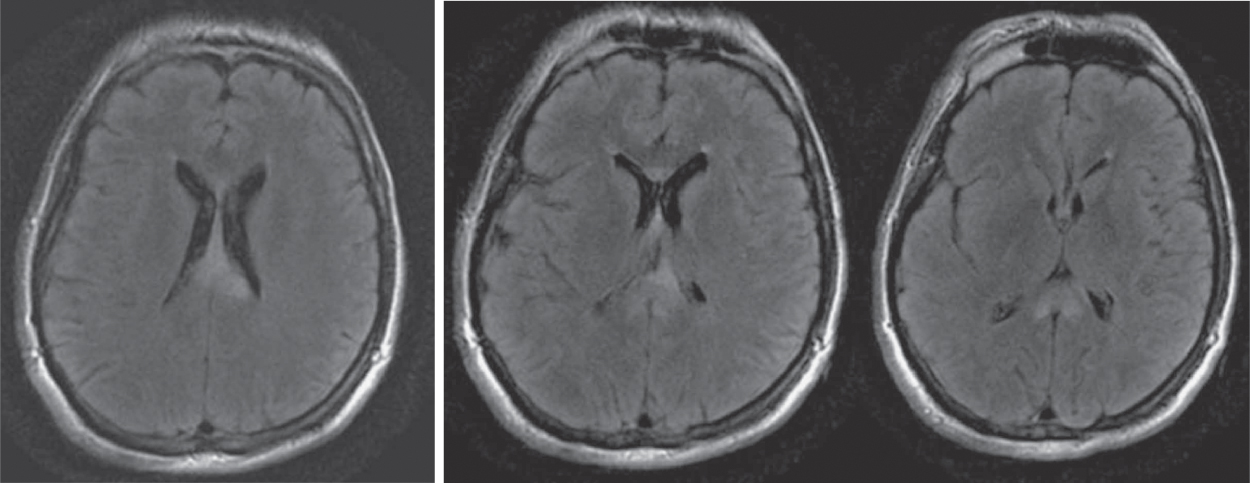

Hình 43.11 Ví dụ về Sự khác biệt trong Kích hoạt MRI Chức năng được Quan sát trong Mẫu Đối tượng bị Chấn thương Sọ não và Nhóm chứng Khỏe mạnh trong Nhiệm vụ Trí nhớ Làm việc Bằng lời nói